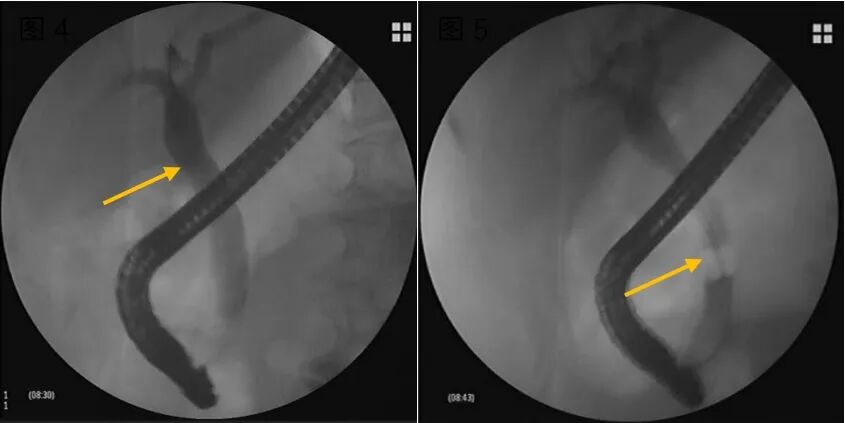

3.胆道炎性病变:如原发性硬化性胆管炎,可利用胆道子镜评估管壁的炎症程度,并使用球囊或探条扩张狭窄部位,改善胆道引流。10.png

胆道子镜见肝门部胆管狭窄,结节状隆起,表面见粗大扭曲新生血管,子镜直视下精准活检提示“腺癌”